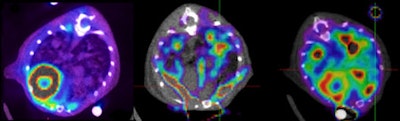

Given our common background, the response can only be PET. FDG-PET is indeed the single area of MI with the largest clinical application at present, especially in oncology, and holds further potential for developments. In the future, it's easy to predict that the use of other radiopharmaceuticals will widen the application in many clinical settings, from neurology to infective disease.